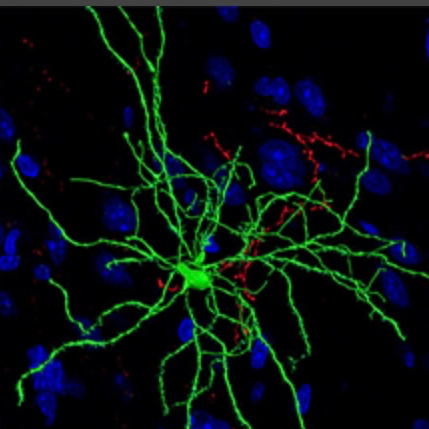

The next few studies demonstrate some of the physical changes occurring in these regulatory inter neurons in the NAC. These are medium spiny neurons and they are…spiny.

This study looked at neuroplastic structural changes occurring in medium spiny neurons (MSN). Red = cocaine white = saline

Dendrites are shown. There are these tiny spines you can see projecting along the dendrites. Changes in the number of these little spines have been noted in addiction which would affect the sensitivity of the cells. Here white bars represent saline control and red bars density of spines following cocaine administration at 4 and 24 hours.

Shell and core are different regions of the NAC. One day after a dose of cocaine there are changes in spine density in the core and shell. This changes neural sensitivity and is thought to further contribute to signaling imbalance. This is hypothesized to be involved in learning.

These neuroplastic changes have been shown to be long lasting and are thought to contribute to relapse.